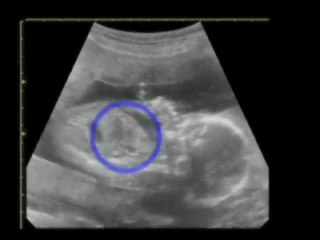

12 Weeks Pregnant Gender Determination Ultrasound

85 chance its a girl - determined at the end where the cursor is pointing\rbr\rbr*confirmed 100 at 20-week ultrasound